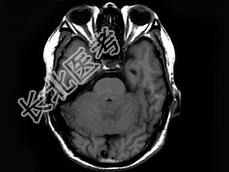

- 单项选择题男,55岁, 头痛40余天,呕吐2天伴共济失调。化验检查: 脑脊液蛋白:2006mg/l, 细胞数60个/mm3MRI平扫显示不佳,增强扫描后见脑膜强化及脑内小结节状强化以脑膜强化为明显, 据此最可能的诊断为 ( )